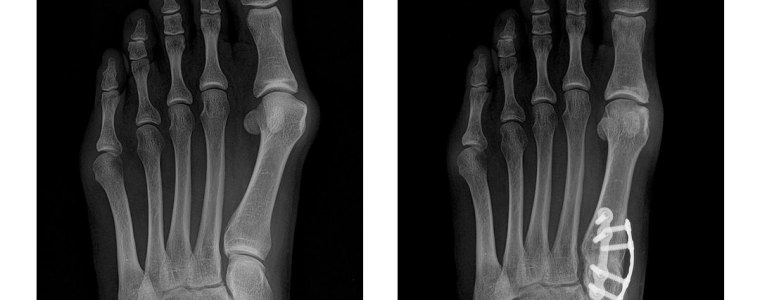

We utilize state-of-the-art treatments, including Lapiplasty®, Radial Pulse Therapy, PADnet®, Digital Radiology, and Swift®, to ensure accurate diagnoses and effective solutions.